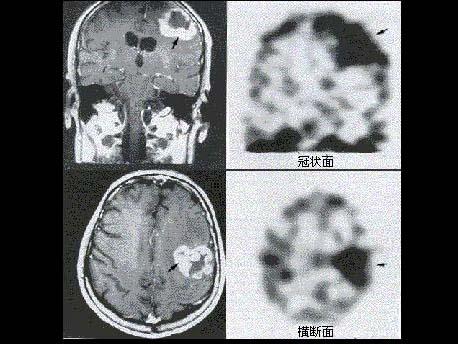

[单选题]男性患者恶性脑肿瘤术后6年复查,有放疗病史,无明显症状,行MRI及99Tcm-ECD脑血流灌注显像,后者提示局部脑血流减低,行201Tl脑显像如图,诊断是()。A . 箭头示手术瘢痕形成B . 箭头示液化坏死区C . 箭头示肿瘤复发D . 箭头示肿瘤脑转移E . 以上都不是

Tc

-ECD脑血流灌注显像,后者提示局部脑血流减低,行

Tl脑显像如图,诊断是()

A.箭头示手术瘢痕形成

B.箭头示液化坏死区

C.箭头示肿瘤复发

D.箭头示肿瘤脑转移

E.以上都不是